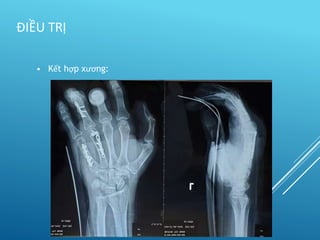

• Kết hợp xương:

– Xuyên đinh

– Vit

– Nẹp

– Bất động ngoài

 Tôn trọng khớp